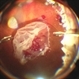

Philip J. Polkinghorne, MD (May 5 2017)No, I am sorry to say it was retained PFC! I believe what happened was the PFC bubbles were trapped in the anterior vitreous at the time of surgery because of overfilling the vitreous cavity. Post operatively the bubbles were obvious as the PFC migrated out of that compartment.

Suber S. Huang, MD, MBA, FASRS (May 5 2017)Nice example of PFC fish-egging. Was PFC retained to assist inferior RD? Pretty common to migrate anteriorly. Well done.

- retina surgery complications, perfluorocarbon fluid, retained perfluorocarbon

- Slit lamp photograph takien one week after retinal detachment surgery where perfluorocarbon liquid was used to re-attach the retina.